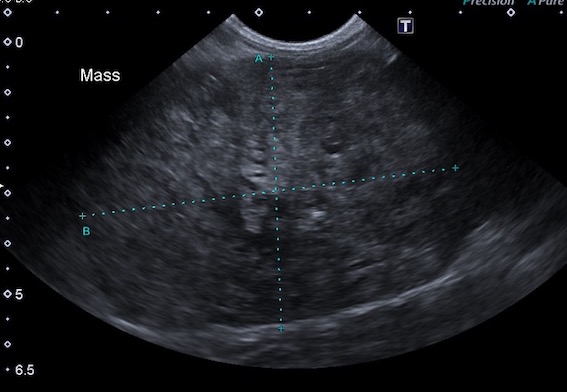

超音波検査画像です。

腹腔内に巨大なしこり(直径約8cm)が認められ、脾臓腫瘤であることが分かりました。